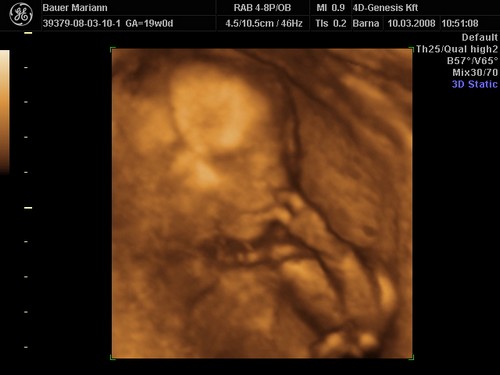

lányok tegnap bevettem egy maltofer vasat és olyan hasmenésem volt most reggel hogy hajjaj ez normális :?: na meg két pici tűszúrásnyi piros pötty lett a pocakomon,jujj megyek mert 10re oda kelll érni a genesisbe látjuk a kicsiket :D jajjj de jó

KépetKépetKépet

Drága picikéim nem voltak túl szereplős hangulatukba úgy kellett kikönyörögni őket a méhlepényből,és még igy sem letek túl élesek a képek.jázmin 266gr ,amy 300gr,jázmin egyszer úgy fejberúgta amyt úgy sajnáltam :D olyan édes formás kiscsajok el vagyok ájulva ,szép egézségesek tele pocakkal,megzabálom őket :D

De nekem eltalálták a 4DGenesisben, nálam tényleg 2 kukis van, igaz, én 2 héttel idősebb terhes voltam, mint te az első 4D-s kukucson.